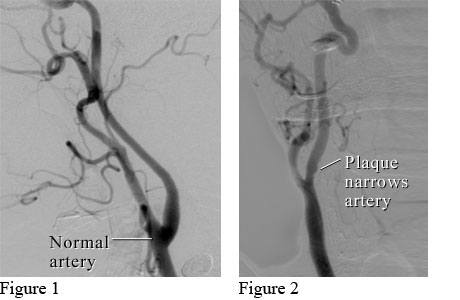

Angiograms of a normal neck artery and a neck artery narrowed by plaque.

Courtesy of Intermountain Medical Imaging, Boise, Idaho.

Figure 1 shows an angiogram (a type of X-ray) of a normal neck artery (carotid artery) with smooth walls. Figure 2 shows a carotid artery that is narrowed by a substance called plaque that builds up in the artery.